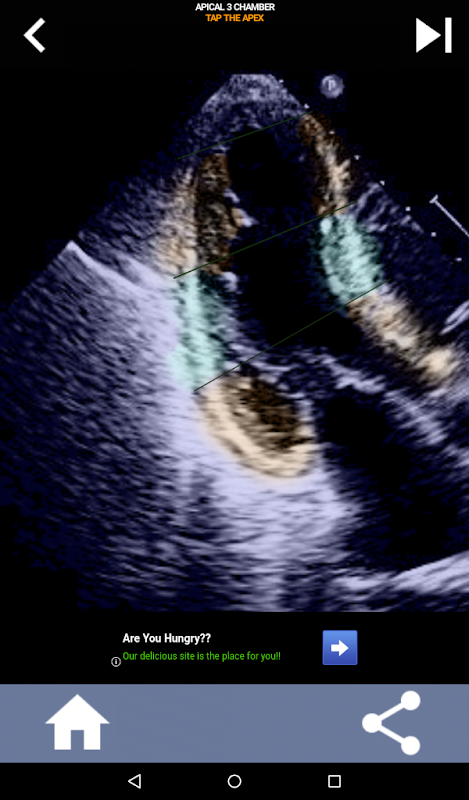

نهج مرئي قائم على الاختبار لتعلم قطاعات القلب AHA: تخطيط صدى القلب

يعد فهم قطاعات القلب من جمعية القلب الأمريكية (AHA) أمرًا في غاية الأهمية بالنسبة لأخصائي تخطيط الصدى القلبي للتواصل بشكل فعال مع طبيب القلب الذي يكتب التقرير. من خلال معرفة المناطق التشريحية المحددة والقطاعات المقابلة لها ، يمكن لأخصائي الموجات فوق الصوتية أن يصف بدقة أي تشوهات أو نتائج ونقلها ، مما يضمن التواصل الواضح والموجز بين كلا المهنيين.

يصبح هذا الفهم حاسمًا بشكل خاص عندما يسعى طبيب القلب إلى التأكد من الموقع الدقيق للمشكلة أو عندما يحدد الطبيب عند الطلب مشكلة داخل منطقة معينة ، مما يدفع أخصائي الموجات فوق الصوتية لعرض المقطع المقابل بدقة ، مثل الجدار الأوسط السفلي. وبالتالي ، فإن امتلاك فهم شامل لمقاطع القلب AHA هو مجموعة مهارات أساسية.

سيختبر هذا التطبيق معرفتك باستخدام صور صدى فعلية ، والتي أجدها غالبًا أفضل طريقة تدريس.